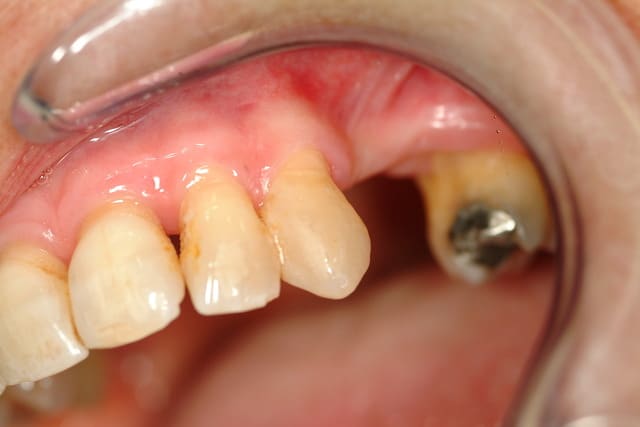

Greffe ? Expansion ?

Vos avis ?

Je suis de l'école greffe...(menton, ramus)

Expansion possible ?

Je pense virer les 35 et 45, et placer 2 implants par côté.

35 et 45 mobiles et sensibles (racines exposées)

Si on revenait à mon cas clinique...mandibule et non maxillaire, avec crêtes très fines, corticales. (zut, le scan est resté au cabinet). Faire une expansion pour une 24, c'est quand même plus facile.